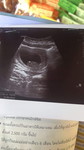

ซาวด์4มิติ ขอนแก่น

อยากทราบราคาซาวด์4มิติ ที่ขอนแก่นค่ะ มีที่ไหนแนะนำ ที่ราคาไม่แรงมากมั้ยคะ

นี่ค่ะ 1800 ส่วนตัวบ้านนี้ซาวด์ที่บ้านไผ่ขอนแก่น 1300 - 1500 เองค่ะ คุณหมอใจดีด้วย